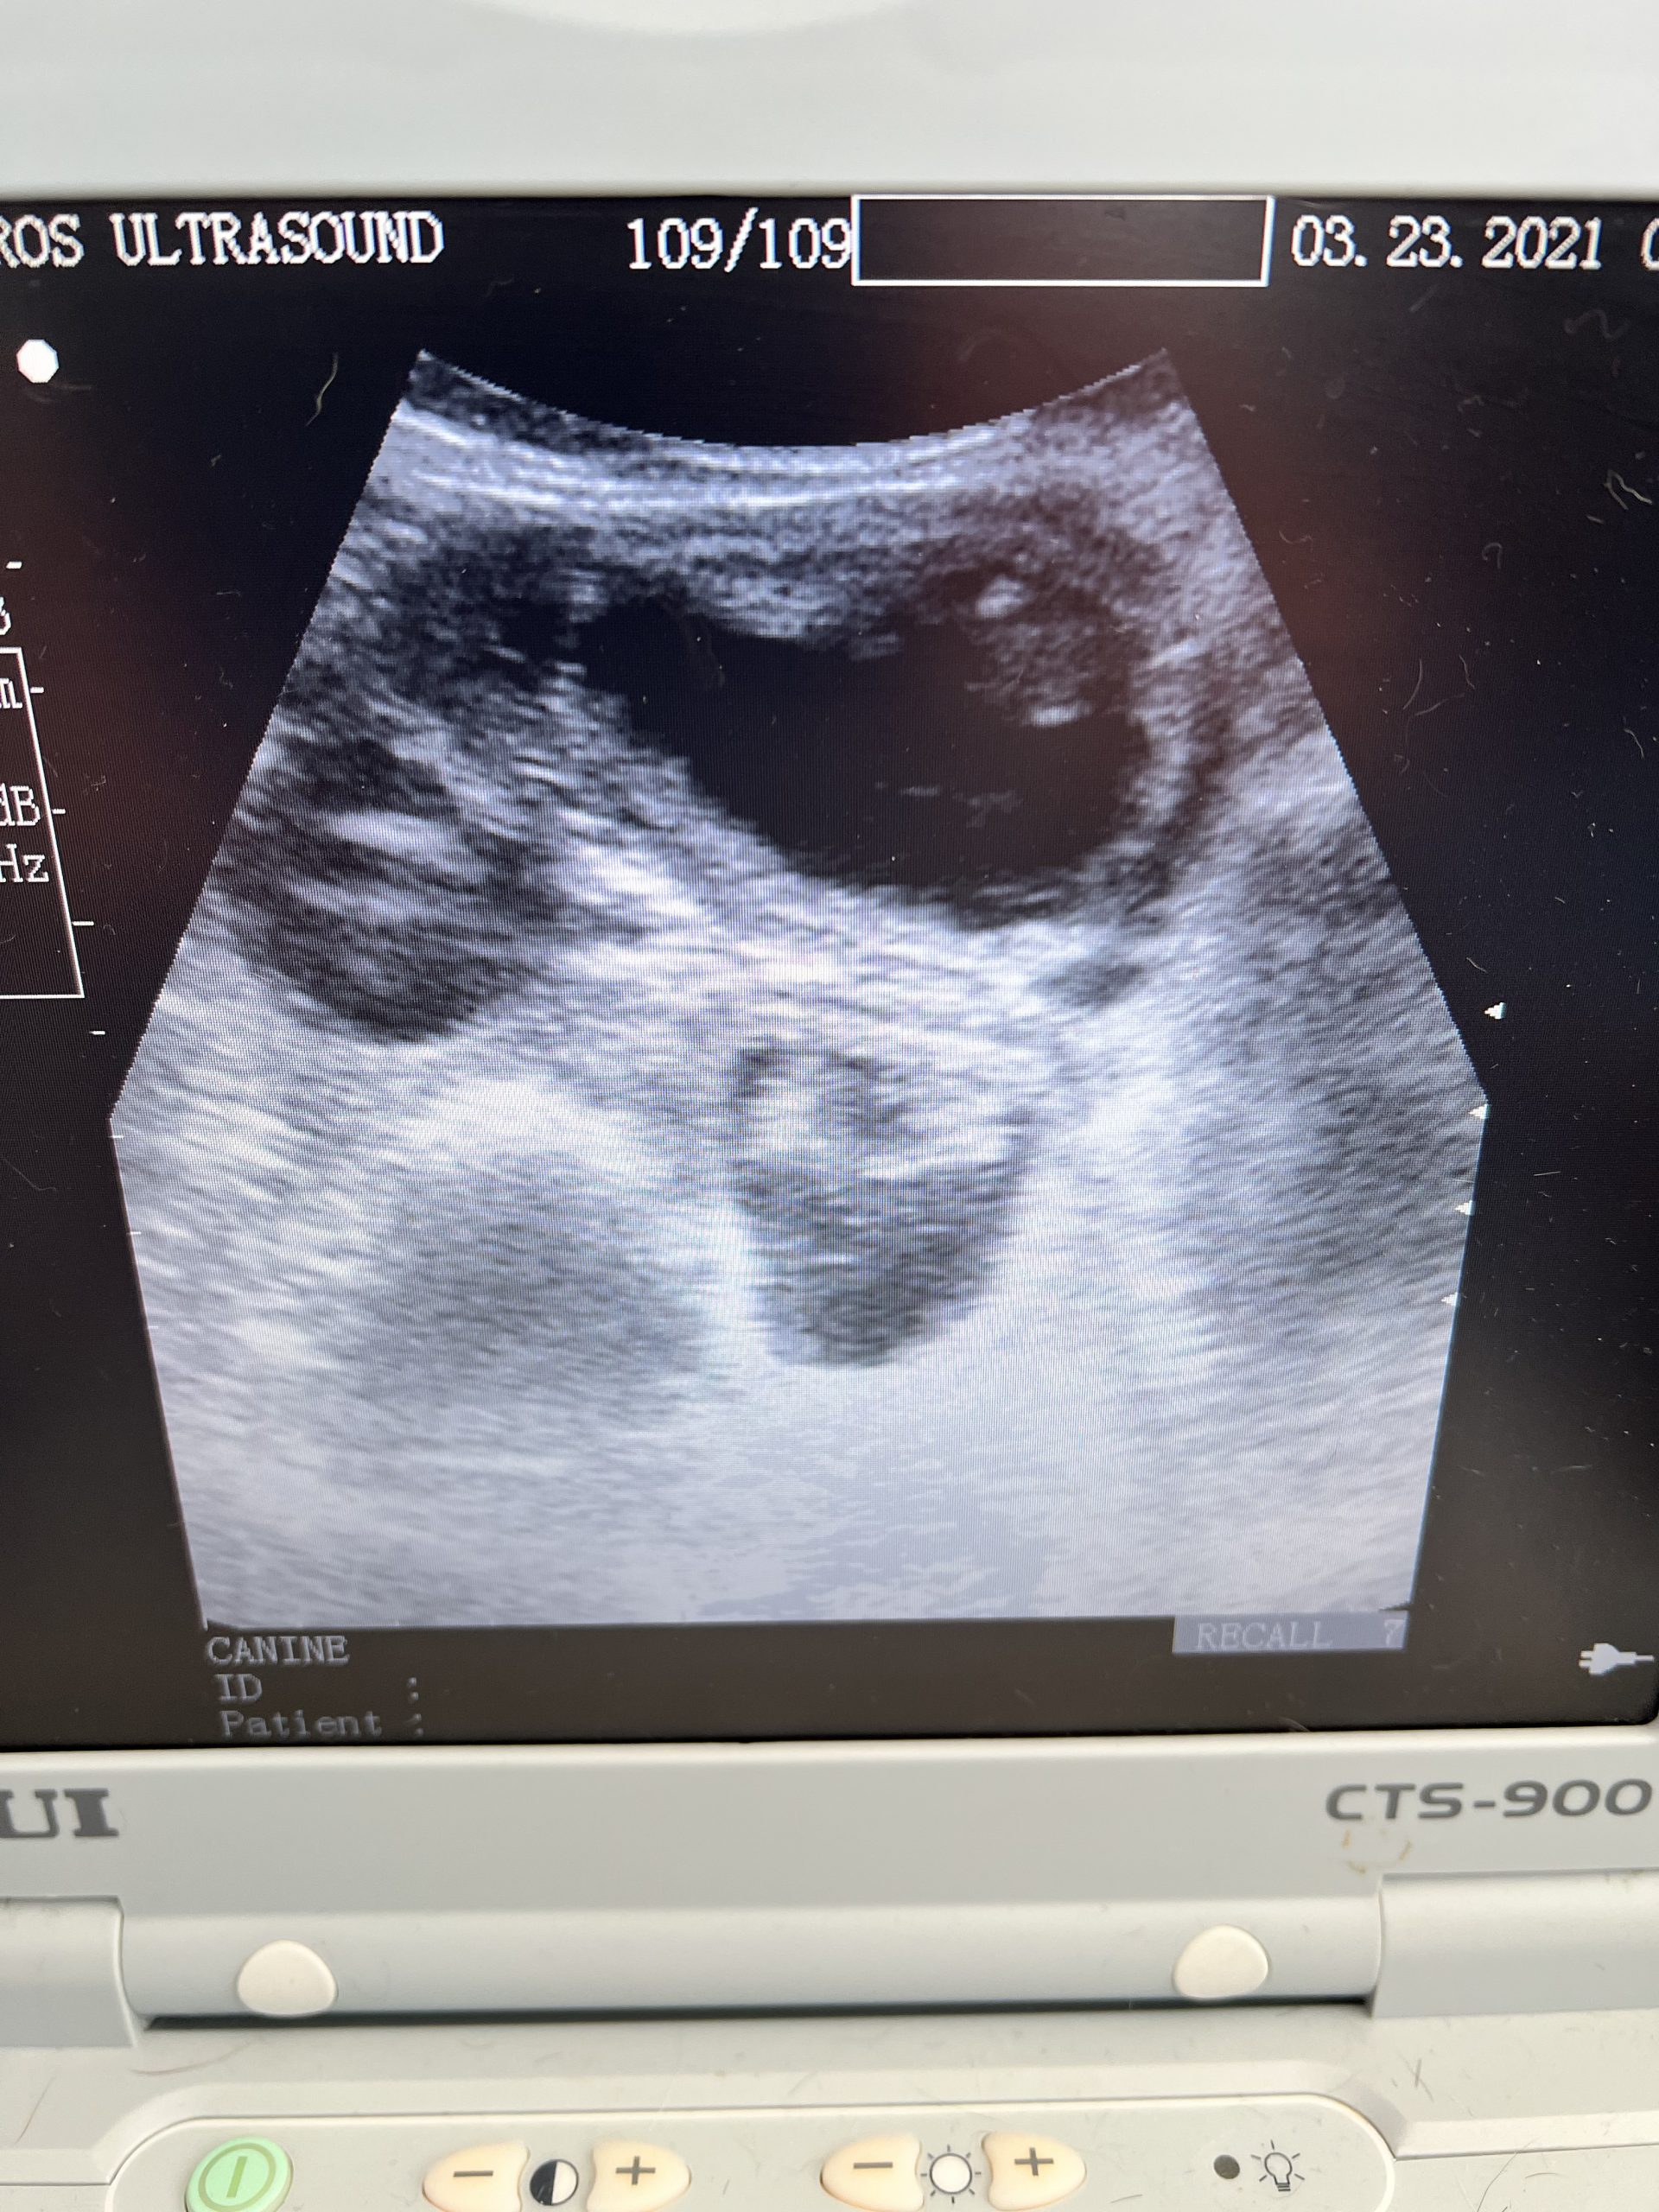

Shadow black standard poodle

5 weeks gestation from mating.

Had the pleasure of meeting and scanning this girl. Pregnancy confirmed and we saw 6 gestational sacs. Excited to see these beauties born, sire is a very handsome black &